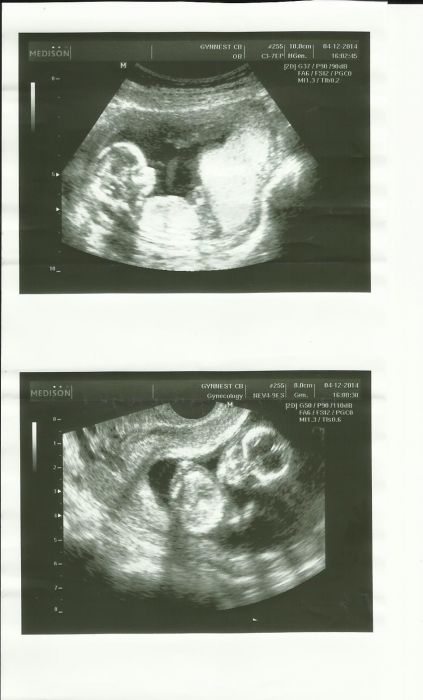

Já na screenu byla a jsem poslaná i na tripl test. Zasílám slíbený ultrazvuk.